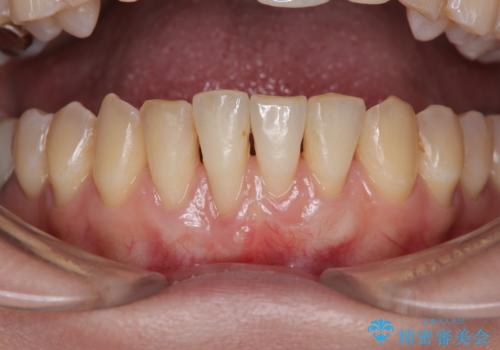

- 他院で矯正治療を終えた結果、下顎前歯の歯肉が退縮してしまい、歯根が見えていることが気になるとのことで来院された患者様です。

歯肉退縮に対して、上顎からの結合組織移植術(CTG)により、歯根の被覆を行うとともに、歯肉の厚みを増すことで将来の退縮リスクを抑制することとしました。